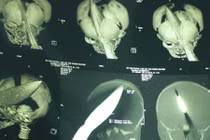

Bé trai 11 ngày tuổi bị đâm xuyên đầu vẫn nguy kịch

Bé trai 11 ngày tuổi bị đâm xuyên đầu ngay tại bệnh viện bởi một người phụ nữ lạ mặt vẫn trong tình trạng nguy kịch.

"Nhìn dao cắm lút vào đầu con, tôi rụng rời"

Chiều 8/8, khá đông người thân, bạn bè của anh Dương Minh Tiền (quê Vũng Liêm, Vĩnh Long) có mặt tại Bệnh viện Nhi đồng 1, TP.HCM để hỏi thăm tình hình sức khỏe bé trai bị đâm xuyên đầu bởi người phụ nữ lạ mặt.

Bé trai bị đâm xuyên đầu: Đã bắt được nghi phạm

(Kiến Thức) - Theo Bệnh viện Đa khoa tỉnh Vĩnh Long, nghi phạm vụ bé trai 11 ngày tuổi bị đâm xuyên đầu đã bị bắt giữ, người này là phụ nữ khoảng 50 tuổi.

Theo Dân Việt, nghi phạm trong vụ bé trai 11 ngày tuổi bị đâm xuyên đầu đang được lực lượng công an giám sát chặt chẽ. Đến chiều tối 8/8, mọi thông tin về đối tượng này vẫn chưa cung cấp cho báo chí.